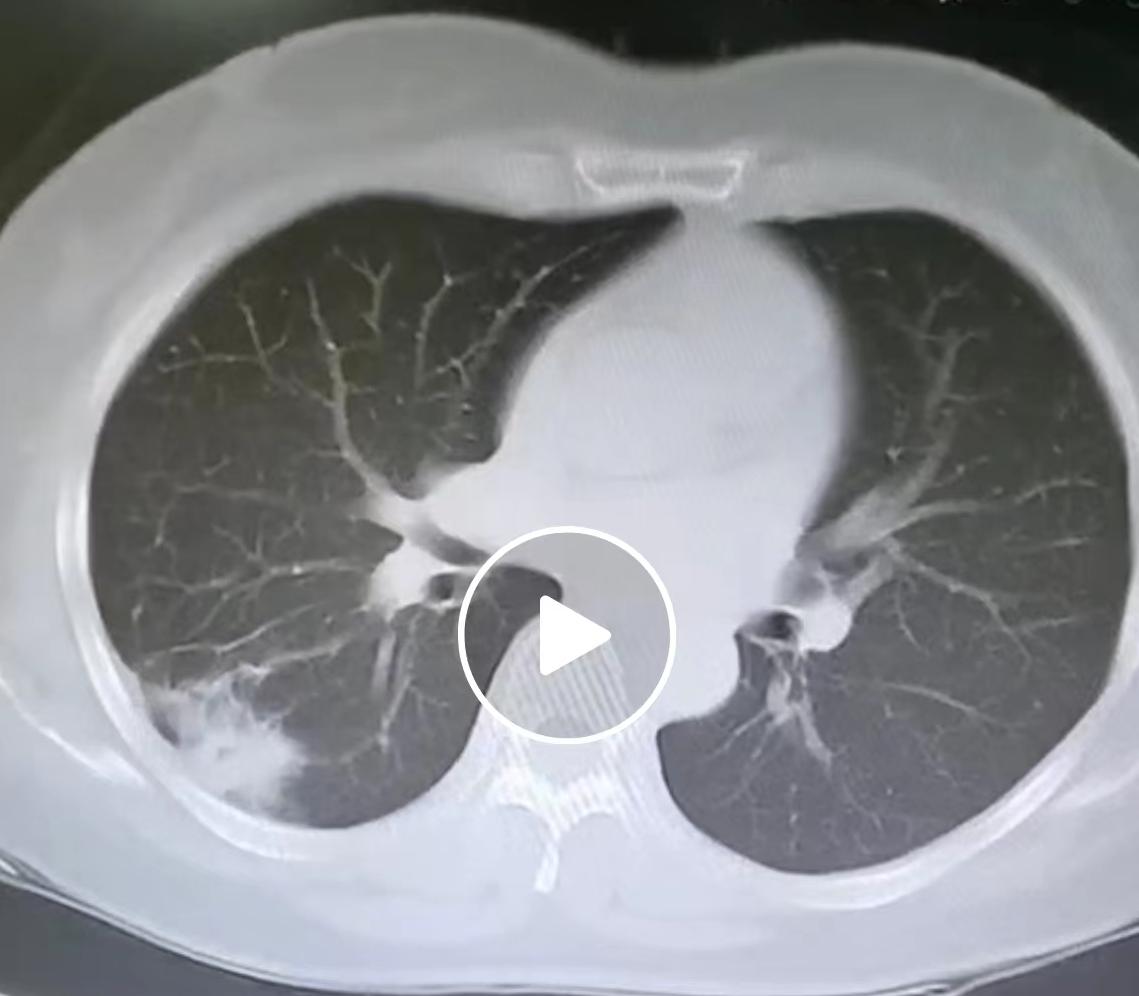

体检查出肺结节,到底多大才要做手术?我的临床原则讲给您听......最近碰到很多

科普做得好=手术差?我用两台一模一样的肺结节手术,说句大实话!刚连做两台肺小结节

20多年前,胸部CT体检可没现在这么普遍,那会儿大家体检,大多也就做个基础项目,

接到一位42岁男士的电话,语气特别急,看得出来是真慌了!他之前体检发现一个8mm